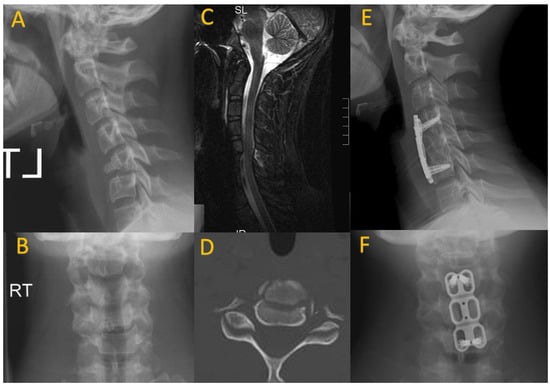

Subaxial cervical spine injuries include ligamentous injuries, anterior column injuries, posterior column injuries, and combined anterior and posterior column injuries. Ligamentous injuries can be diagnosed using dynamic X-rays. Horizontal displacement of one vertebral body on another in the young pediatric spine can be considered normal when up to 4 mm; cervical vertebral subluxation of greater than 4.5 mm should raise concern for ligamentous instability [26]. Anterior column injuries include teardrop fractures, longitudinal fractures, wedge compression fractures, and burst fractures (Figure 3). Posterior column injuries involve injuries to the facets, lamina, pedicles, or spinous process. Combined anterior and posterior column injuries, involving both ligamentous and osseous injury, are less common in the pediatric population, but when present are highly unstable and often secondary to a high-energy mechanism [27].

Figure 3.

A 14-year-old male who presented after hitting a tree while snowboarding. On presentation he complained of transient weakness and persistent neck pain. He was found to have a C5 teardrop fracture on sagittal and AP cervical spine X-rays (A,B). There was interspinous ligament injury noted on the sagittal MRI STIR sequence (C). CT axial imaging again demonstrated the anterior column fracture (D). He underwent C5 corpectomy with anterior C4–6 instrumentation and allograft interbody strut (E,F).